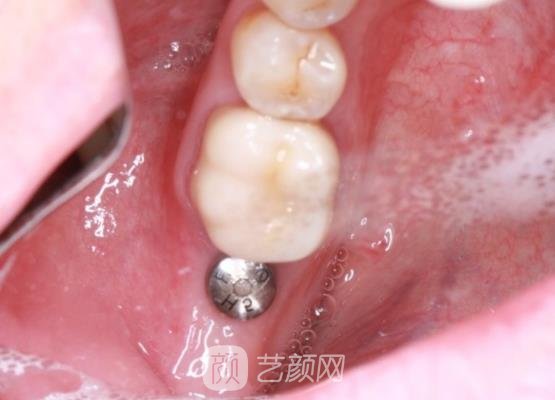

根据我的检查报告,为我选择出适合的种植,人体也制定出适合的调节方案,看了收费觉得很合理,并没有乱收费等情况。医生在全过程当中操作的很认真,对于细节也掌握的很好,由于注射了麻药,所以也没有太大的感觉。

每天都在期待当中度过以后照着镜子观察局部的恢复情况,前两天特意去医院佩戴了烤瓷牙,冠医生说我恢复得很稳定,现在自己了种植牙,目的真的是很开心呀。

经过一段时间的修养,局部的状况越来越稳定,而且口腔也没有异物感,因为种植牙不需要佩戴卡槽或者是基托。现在自己在微笑的时候,身边很多朋友都说,从外观上来看也没有什么异样感,而且颜色和自然牙齿颜色也相接近,感觉吃饭的时候也更加的便利了。